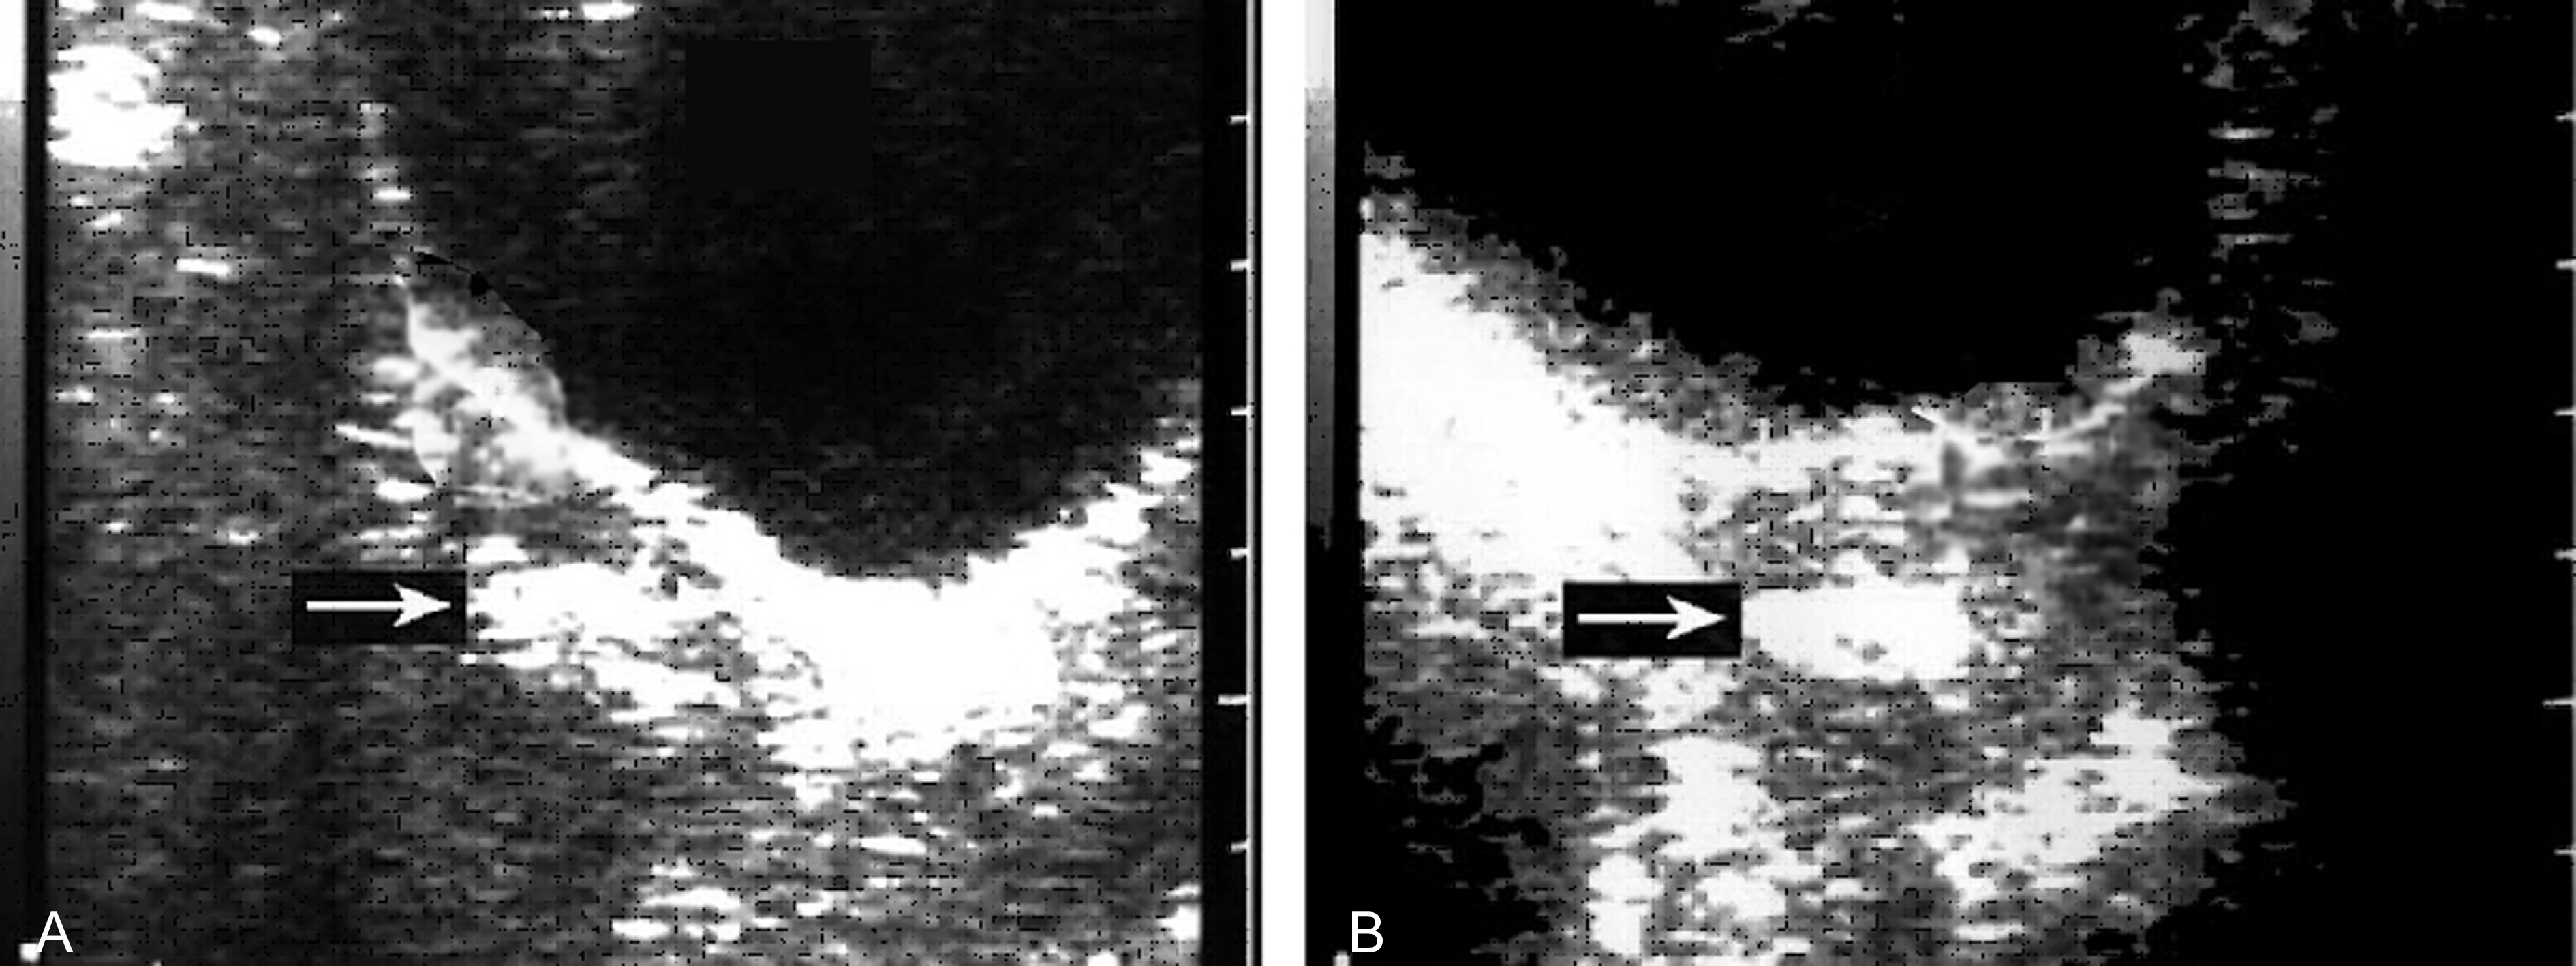

妊娠囊大小正常或较正常缩小,位置下移、变形(图3A)、边缘失去连续性;内部胚胎或胎儿活动消失,心脏搏动明显变弱或不规律、或消失(图3B);如果绒毛膜下血肿超过15ml以上并波及胎盘基底部,即便没有孕囊移位和胚胎死亡,多数也将以流产结束妊娠。

图3 难免流产声象图:变形的孕囊(GS)